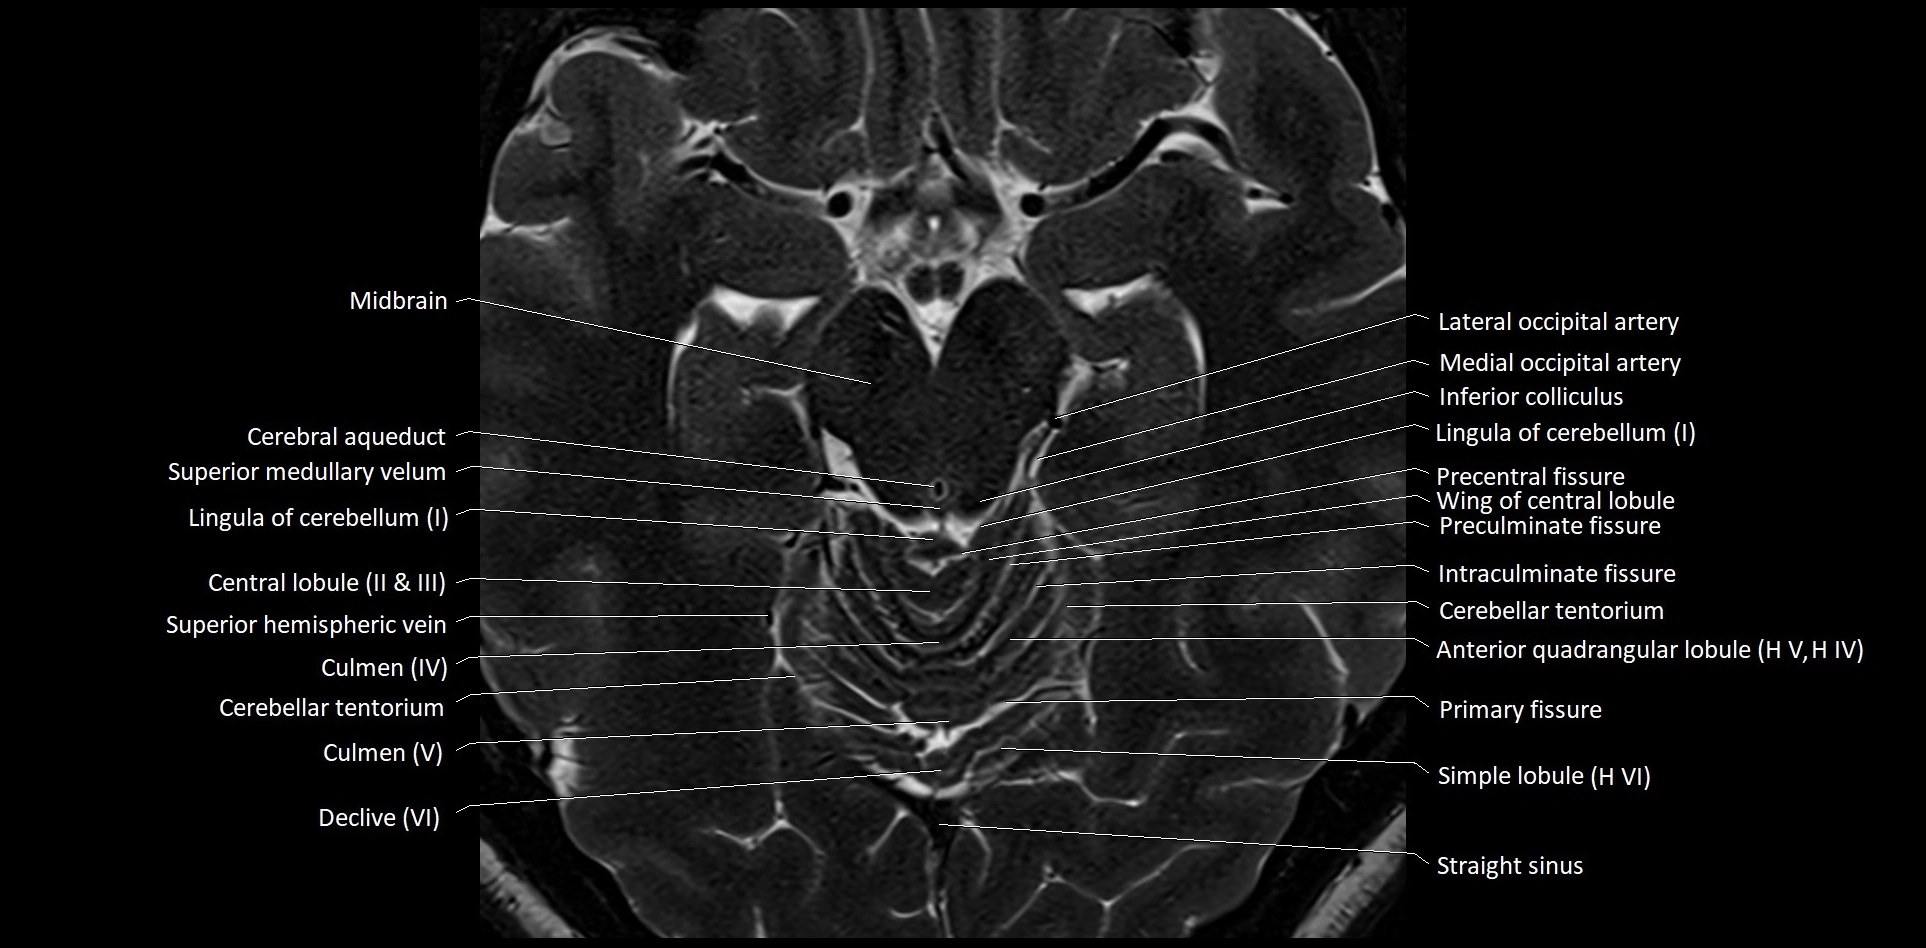

MRI images